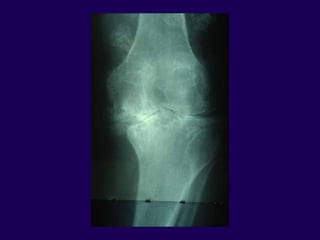

Total Knee Arthroplasty

Radiographic Evaluation

Weight Bearing X-rays

—Extent of joint space

narrowing

—Ligament stretch out

—Subluxation of femus on tibia

Surgical Techniques

Varus Knee

1. Pes anserinus

2. Joint Capsule

3. Deep Tibial Collateral

4. Semimembranosus

5. Posterior Medial Capsule